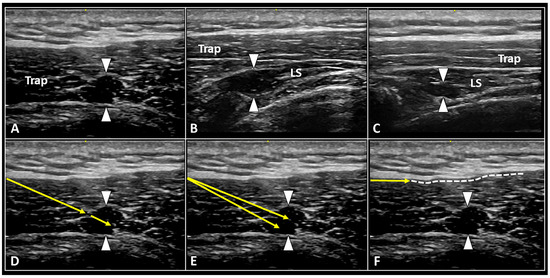

3.4.1. Injection and/or Dry Needling of the MTrPs

- Ricci, V.; Özçakar, L. Ultrasound imaging of the upper trapezius muscle for safer myofascial trigger point injections: A case report. Phys. Sportsmed. 2019, 47, 247–248. [Google Scholar] [CrossRef] [PubMed]

- Ricci, V.; Güvener, O.; Özçakar, L. Injections for myofascial pain: From whodunit to an ultrasound-guided technique. J. Ultrasound Med. 2022. [Google Scholar] [CrossRef] [PubMed]

| MTrP | Injection and/or dry needling of the hypoechoic painful nodule | Multiple back/forward needle movements Fan-like technique |